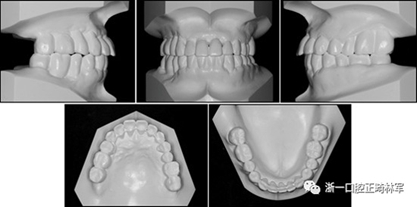

在治療結(jié)束時,通過拔除下頜側(cè)切牙,間隙閉合和推上頜牙列向遠中,實現(xiàn)了前牙良好的對齊,尖牙I類關(guān)系以及合適的覆合和覆蓋?;颊叩膫?cè)面貌輪廓得到改善,并且她的嘴唇不適得到緩解。下頜右側(cè)第二磨牙直立,后牙被修復(fù)并恢復(fù)穩(wěn)定咬合(圖10和圖11)。牙周治療和牙周病的控制導(dǎo)致牙周袋深度的穩(wěn)定,并且在探測時沒有出血。

圖11.治療后牙齒的石膏模型

治療后頭影測量分析顯示上頜切牙的傾斜和唇部相對于E線的位置都得到改善(表II)。治療前后頭影測量圖的疊加顯示上頜和下頜切牙的向后移動伴隨著上頜切牙的推入。垂直維度在跨學(xué)科正畸綜合治療后被保持。三維模型的疊加顯示了上頜牙列的遠中移動,下頜前牙的回縮和上頜右側(cè)尖牙的推入(圖14)。